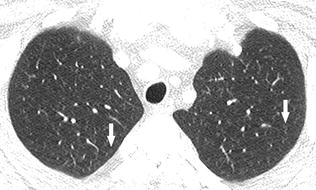

To improve the long-term survival of patients with ARS-ILD novel therapies beyond CS and IS that can prevent refractory fibrosis progression and AE development are required. Respiratory bronchiolitis associated interstitial lung disease RB-ILD is a recently described clinicopathological entity that occurs almost exclusively in current heavy cigarette smokers. And include in order of frequency central bronchial wall thickening 90 peripheral bronchial wall thickening 86 centrilobular.

The clinical and physiologic features of respiratory bronchiolitis RB-interstitial lung disease ILD have been previously described. In a subset of patients however this is the only pathologic finding and seems to account for clinical interstitial lung disease.

It is a form of idiopathic interstitial pneumonia associated with smoking. The clinical and physiologic features of respiratory bronchiolitis RB-interstitial lung disease ILD have been previously described. In a subset of patients however this is the only pathologic finding and seems to account for clinical interstitial lung disease. Few cases have been reported in the literature and no studies have been carried out on the effect of treatment which currently consists of smoking cessation with or without corticosteroids. Respiratory bronchiolitis refers to a histological finding that can be often seen in heavy smokers. Symptoms include cough and breathlessness during exertion. The concept of RBILD has changed over time with the recognition that histologically and radiologically RB and RBILD are usually indistinguishable. Portnoy J Veraldi KL Schwarz MI Cool CD Curran-Everett D Cherniack RM King TE Brown KK. Respiratory bronchiolitisassociated interstitial lung disease RBILD is a syndrome of small airway inflammation and interstitial lung disease occurring in smokers.